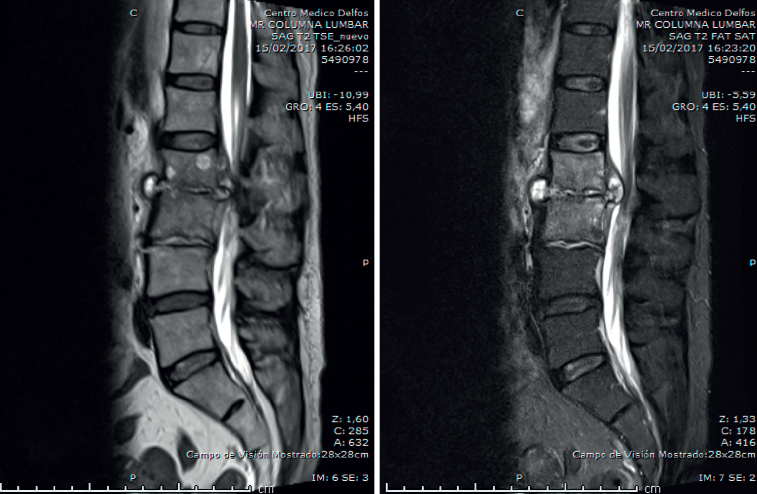

Figura 4. Resonancia magnética a los 3 meses del ingreso. Sagitales T2 y STIR.

En la RM lumbar (Figura 4) se observaba desaparición de los abscesos preexistentes. Discopatía evolucionada.